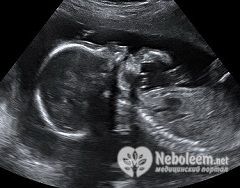

Размер плода на 20 неделе беременности в длину составляет около 26 см, весит он уже 310-350 г. С этого срока для оценки развития будущего младенца на УЗИ в 20 недель беременности контролируют и другие показатели – диаметр головы, грудной клетки и живота.

Плановое УЗИ на 20 неделе беременности является необходимым минимумом исследований для всех женщин на этом сроке. Всего за нормально протекающую беременность женщине рекомендуют пройти не менее 3 ультразвуковых исследований в 10, 20 и 30 недель.

По результатам УЗИ оценивают размер плода на 20 неделе беременности и его соответствие сроку. УЗИ в 20 недель беременности чаще всего позволяет определить половую принадлежность будущего малыша.